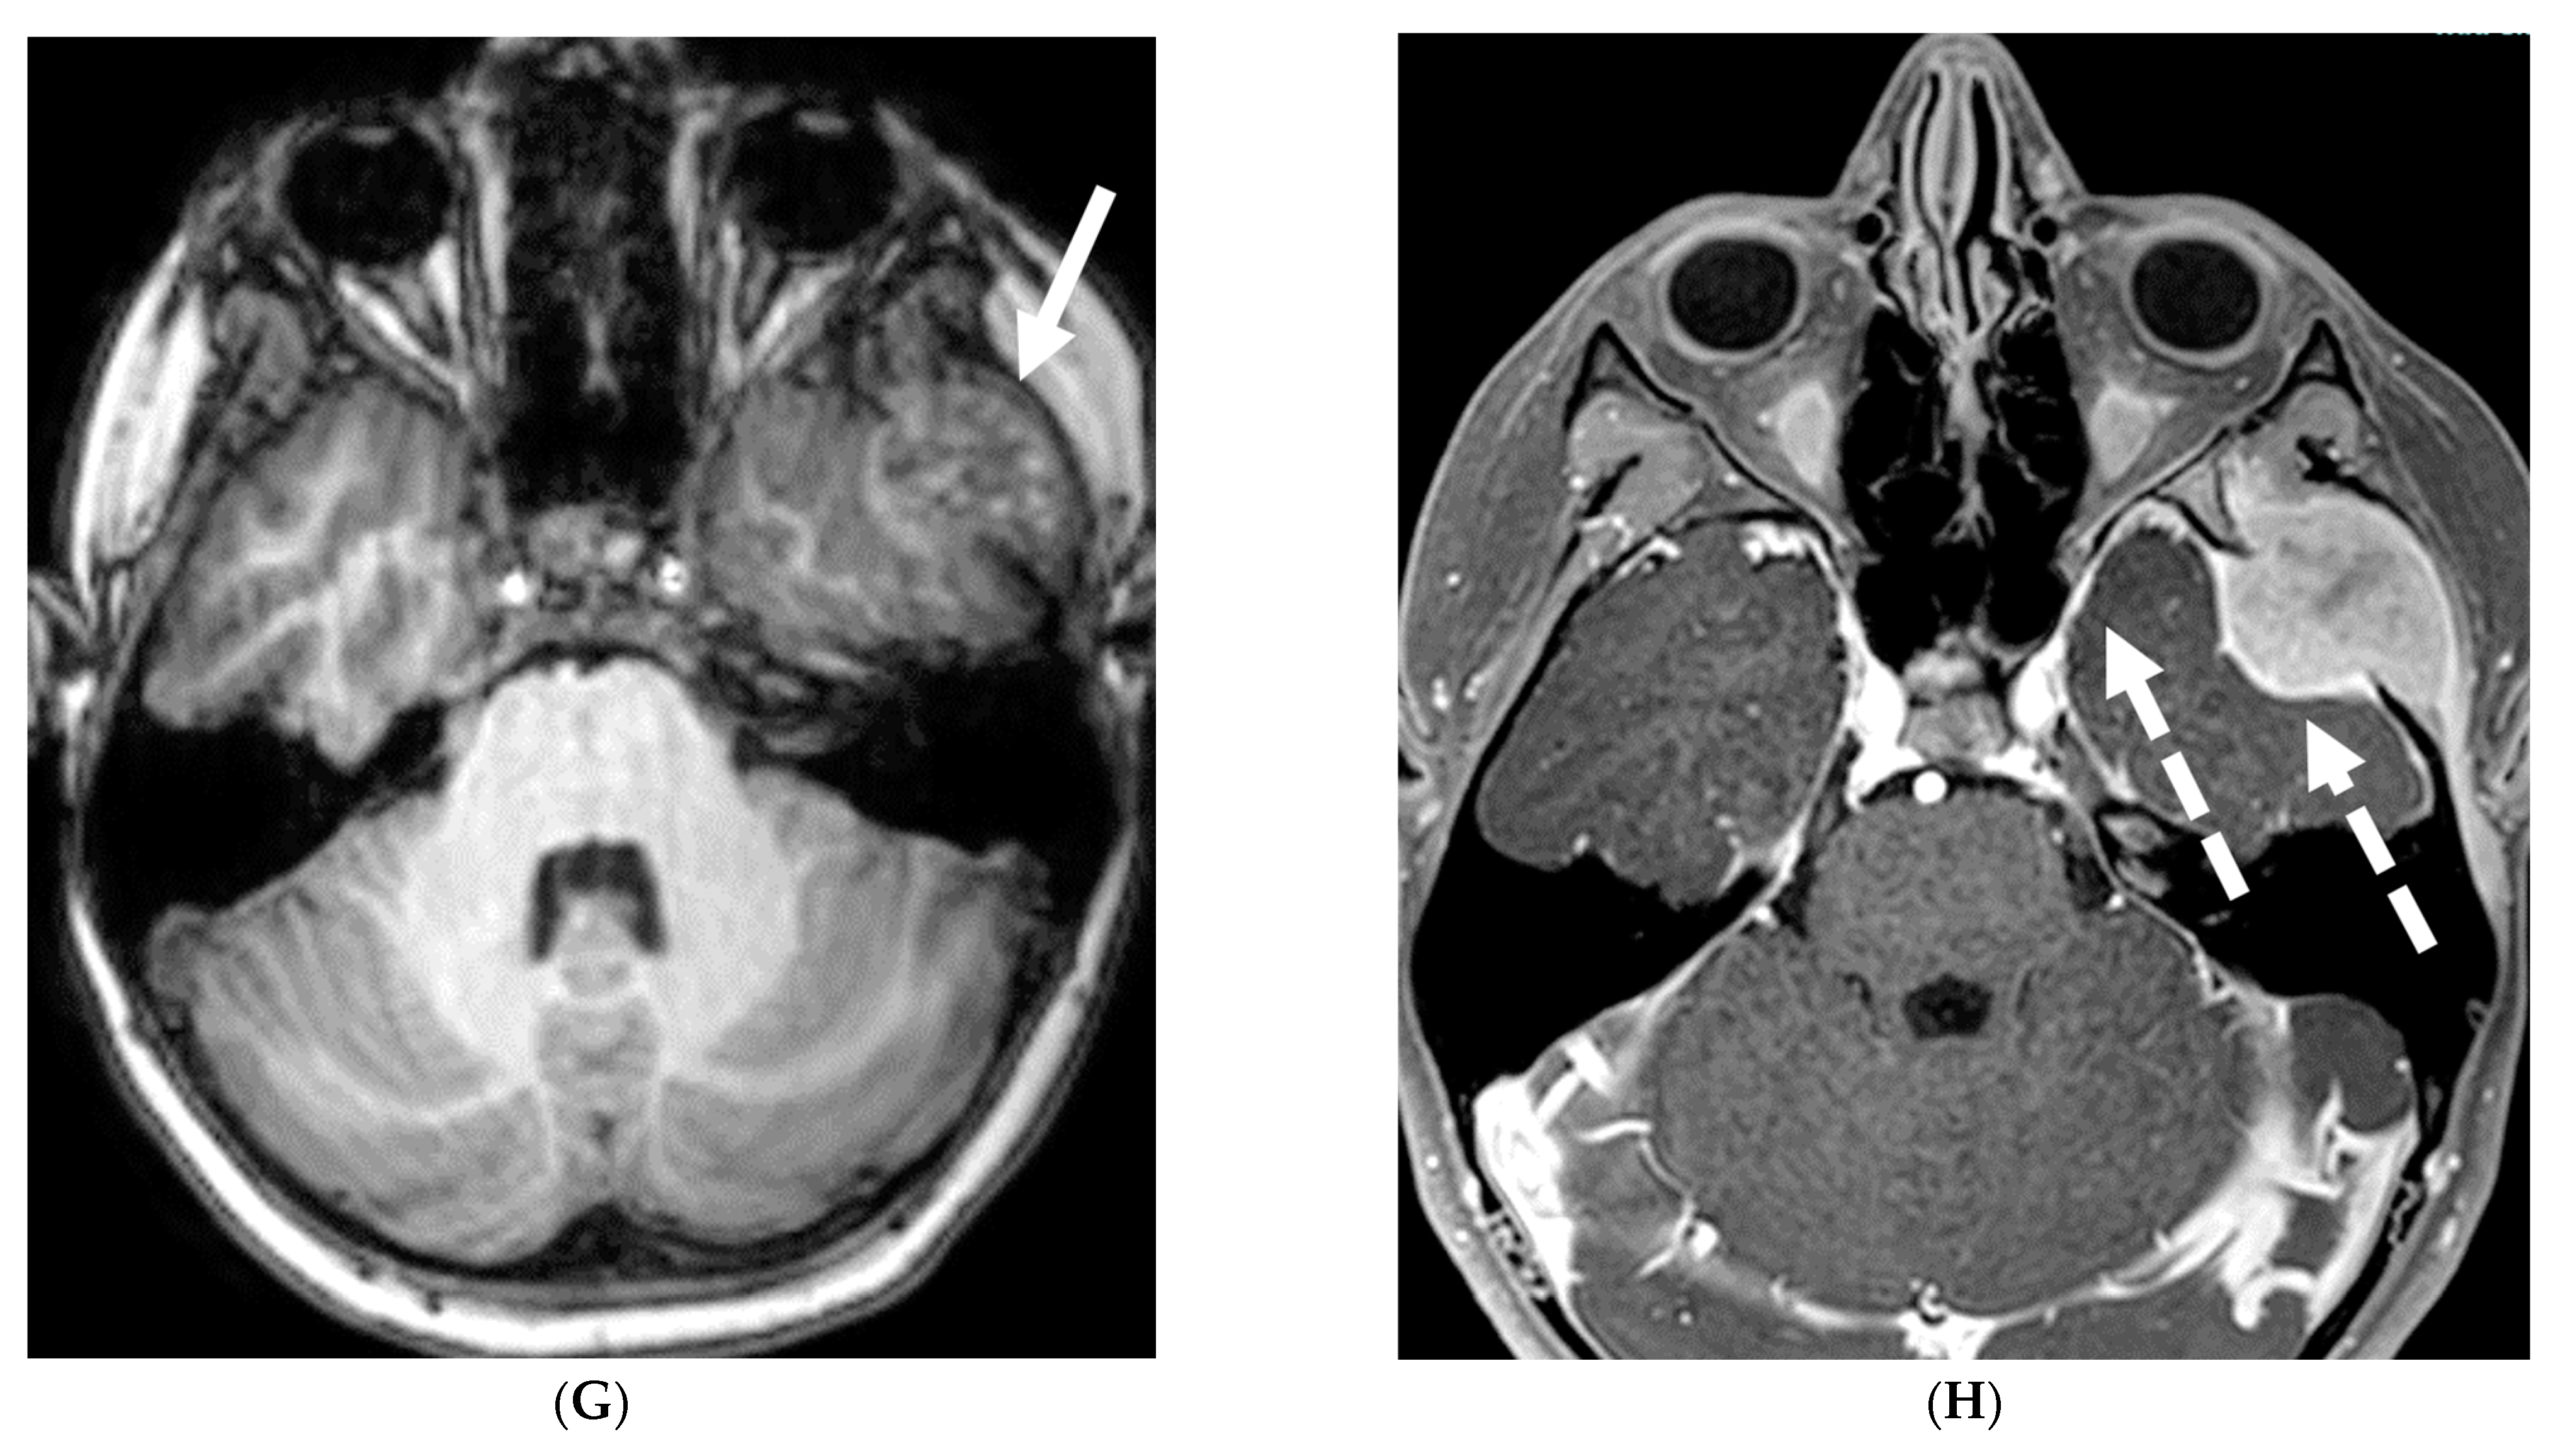

4.5. Moya Moya

Moya moya disease (MMD) is a complex neurovascular condition characterized by progressive narrowing of the internal carotid terminus and/or the proximal anterior or middle cerebral arteries. Due to chronicity, arterial collateral vessels develop to bypass the narrowing. These collaterals can be basal, leptomeningeal or transdural, arising from perforating arteries, typically coursing through the meninges [90]. These collaterals are often small, weak, and prone to bleed or clot.

MRI, the standard noninvasive imaging modality, shows vascular narrowing on T2-weighted images and collateral vessels [91,92]. FLAIR sequence helps in detecting subtle areas of gliosis or chronic white matter ischemia. While DWI remains the optimal sequence for detecting acute ischemia, SWI helps in detecting acute or chronic microbleeds in addition to prominent deep medullary veins in areas with impaired blood flow (depicted as the “brush sign”). MR angiography defines the disease extent.

In children with moya moya, the LME is termed the “ivy sign” as the appearance resembles creeping ivy (Figure 18) [93]. LME arises due to two key factors in MMD, namely neovascularization and retrograde flow from congested pial vessels [94].

Figure 18.

Axial FLAIR (A), MRA (B), axial ASL perfusion (C) and axial T1 post contrast (D): 7-year-old girl with Down’s syndrome: Abnormal FLAIR hyperintense signal with LME along the right cerebral convexity sulci, predominantly in the frontoparietal region representing “ivy sign” (arrows). Asymmetric decreased perfusion in the right frontal and temporal regions (curved arrows). The M1 segment of right MCA is not visualized with extensive moyamoya vessels (dashed arrows). The M2 and M3 branches of right MCA are asymmetrically attenuated. Bilateral A1 segments are not identified with extensive collateralization and diminutive caliber of A2 and A3 segments (arrow heads).

Although LME is a supportive feature in the diagnosis of moya moya, LME is a marker of collateral vessel status and less LME is a marker of severe clinical symptoms and poor postoperative outcomes [95]. In addition, degree of reduction of LME after surgery has been proposed to be a marker of effective surgery [96].